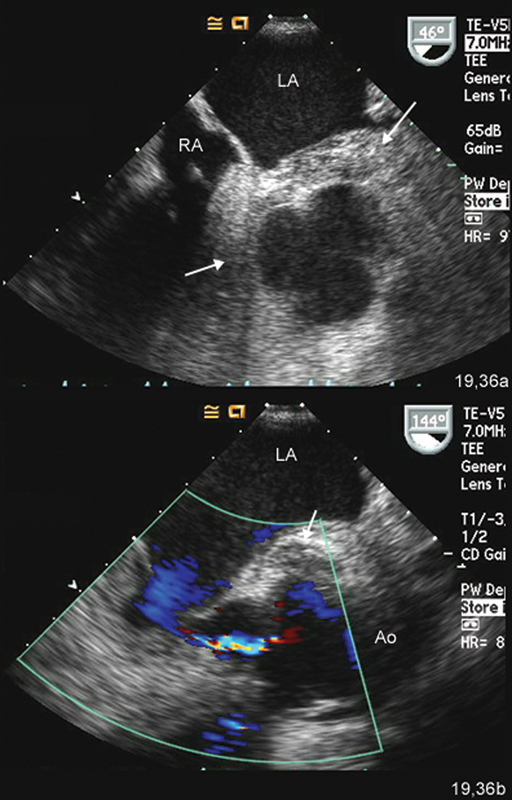

فحوصات تشخيصية لبعض امراض القلب والشرايين التاجية